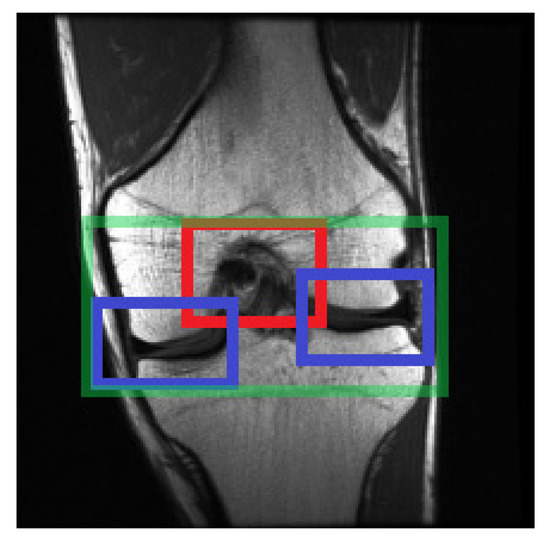

2.4. Selecting the Relevant Area

2.4.4. Structure of the Region of Interest Model